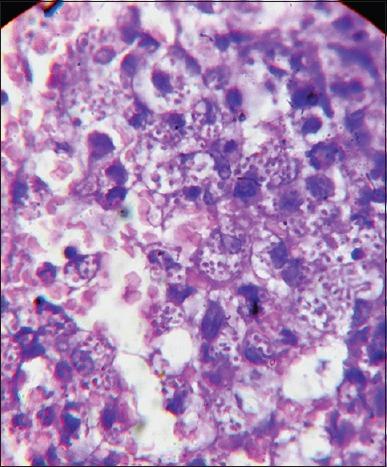

Persistent Skin-colored Papules Over Face in an Immunocompromised Patient.

https://cdn.ncbi.nlm.nih.gov/pmc/blobs/76da/4763628/6fd8d0c63a66/IJD-61-116-g001.jpg